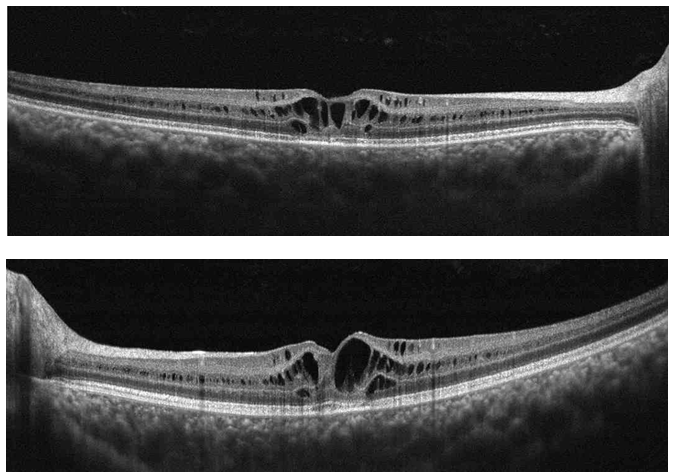

It has been previously reported that high-speed, high-resolution, Fourier domain OCT can evaluate thinning of the retinal nerve fiber layer in these patients.15 Gerth used high resolution OCT to described retinoschisis findings and reported that the fovea, the full-thickness measurement of inner and outer retina thickness as well as volume measurements were increased in patients with retinoschisis. This measurement increase was attributed to the schisis cavities.16 While using time-domain optical coherence tomography, Apushkin suggested that there was no association between visual acuity and full-thickness foveal thickening or cystic area size (Figure 4).17. Newer studies suggest that visual dysfunction is multifactorial, affected by both inner foveal thickening and temporal perifoveal inner retinal thinning. The schisis associated with inner foveal thickening most likely relates to foveal distortion while inner retinal atrophy related to the inner retina of the temporal perifoveal retina may also play a factor in visual dysfunction.16

Figure 4 (Top) Right Eye and (Bottom) Left Eye Cross line OCT. Large cyst like schisis (Bottom).